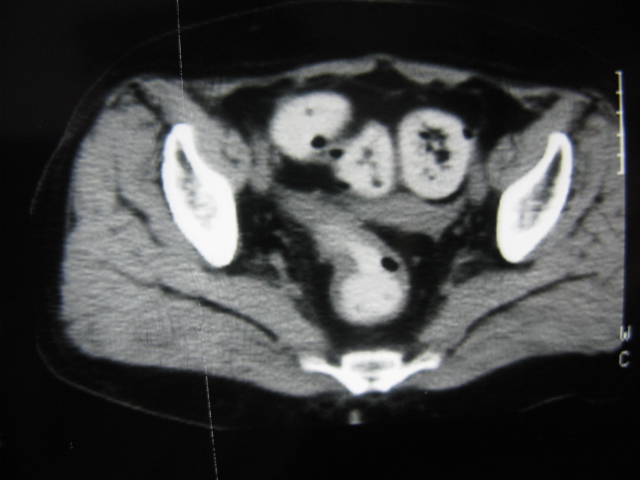

患者,女,64岁,2002年诊断为宫颈癌,当时只做过放,化疗。现在诊断:(1)宫颈癌。(2)直肠癌。请同道们讨论,探讨。另外肠壁为啥密度这么高,ct值约112hu。患者没有做过增强和造影。

高密度的不是肠管影,是肠管内的粪便影

患者直肠病变,排便不畅,粪便硬结造成,更高密度如钡灌肠者都可出现

硬结粪便能有如此高密度影?

我也碰到过几例,最离奇的一例是全结肠呈造影样高密度,患者直肠癌(首次发现),以往没有吃药,只有约半年时间长的胃纳差,排便不畅(据患者说每次大便只能拉出少许黄水)

不一定有意义,可清洁灌肠后复查